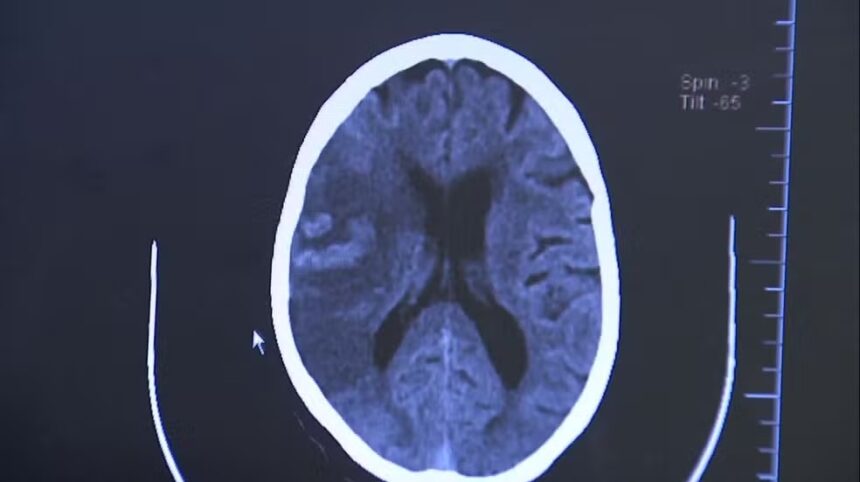

O diagnóstico é feito por tomografia ou ressonância magnética, que permitem identificar a área afetada e o tipo de AVC.